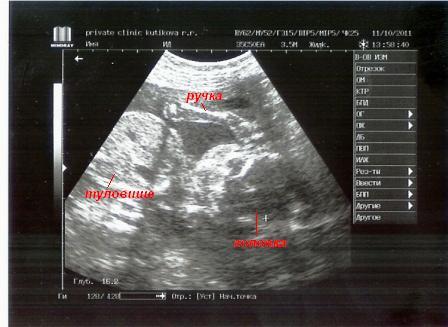

И фото

БПР 40мм

ОГ 143мм

ОЖ 126 мм

ДБ 24 мм

Все в норме